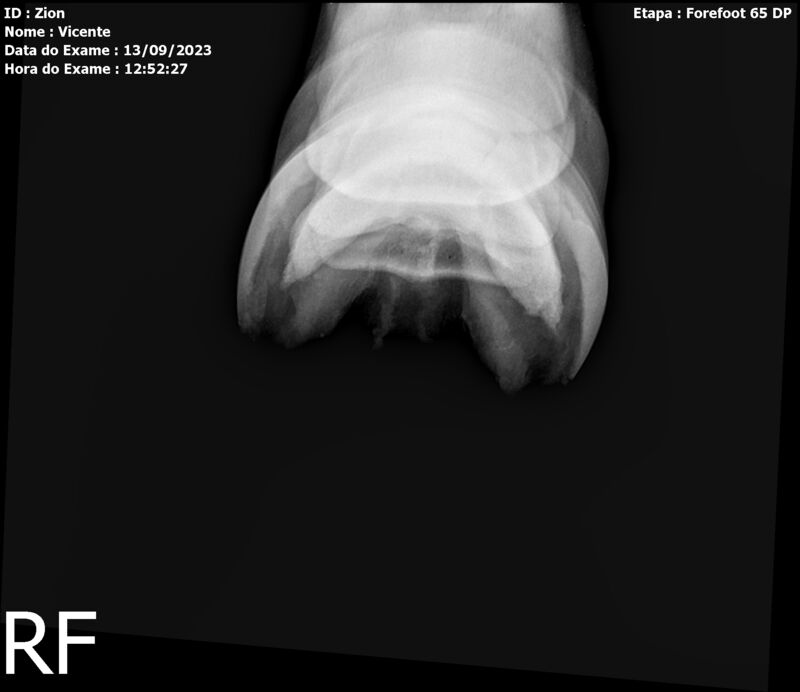

ZION ZC

Raça: BRASILEIRO DE HIPISMO

Sexo: MACHO - POTRO

Nascimento: 17/12/2022

Altura Aproximada: 1,51

Pel.: CASTANHO

Registro: EM AND

Vend.: VICENTE CONTE

Local : PORTO FELIZ/SP